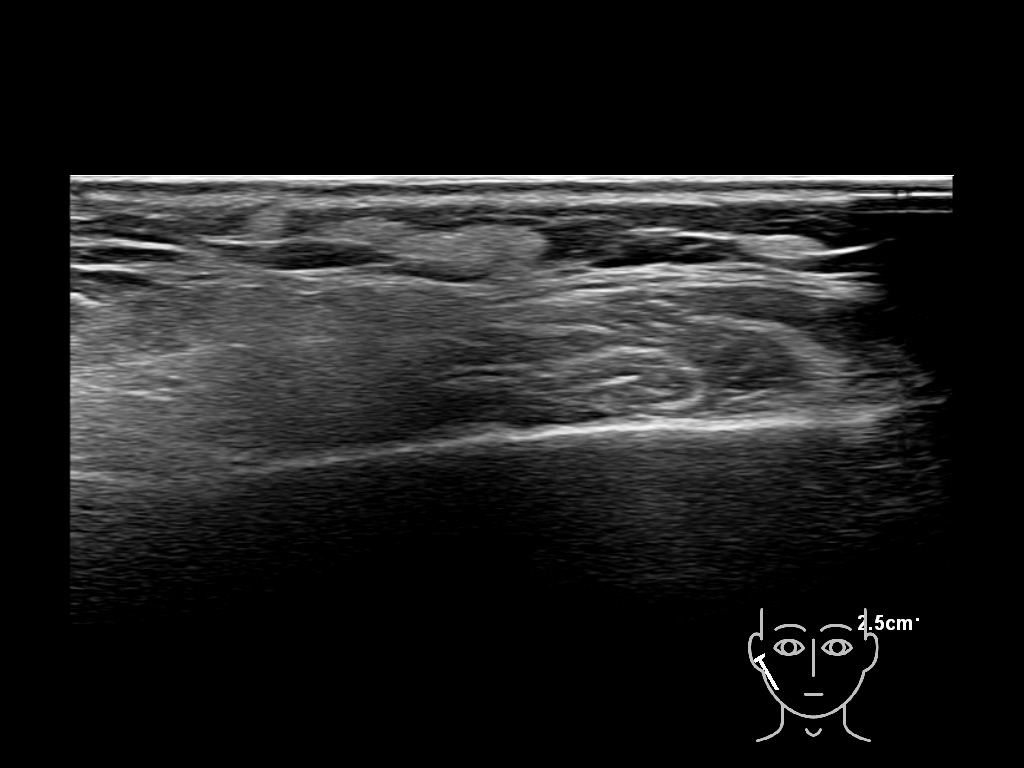

Draw in the image on the right where the fillers are located. To check if your answer is correct, please click on the secondary image.